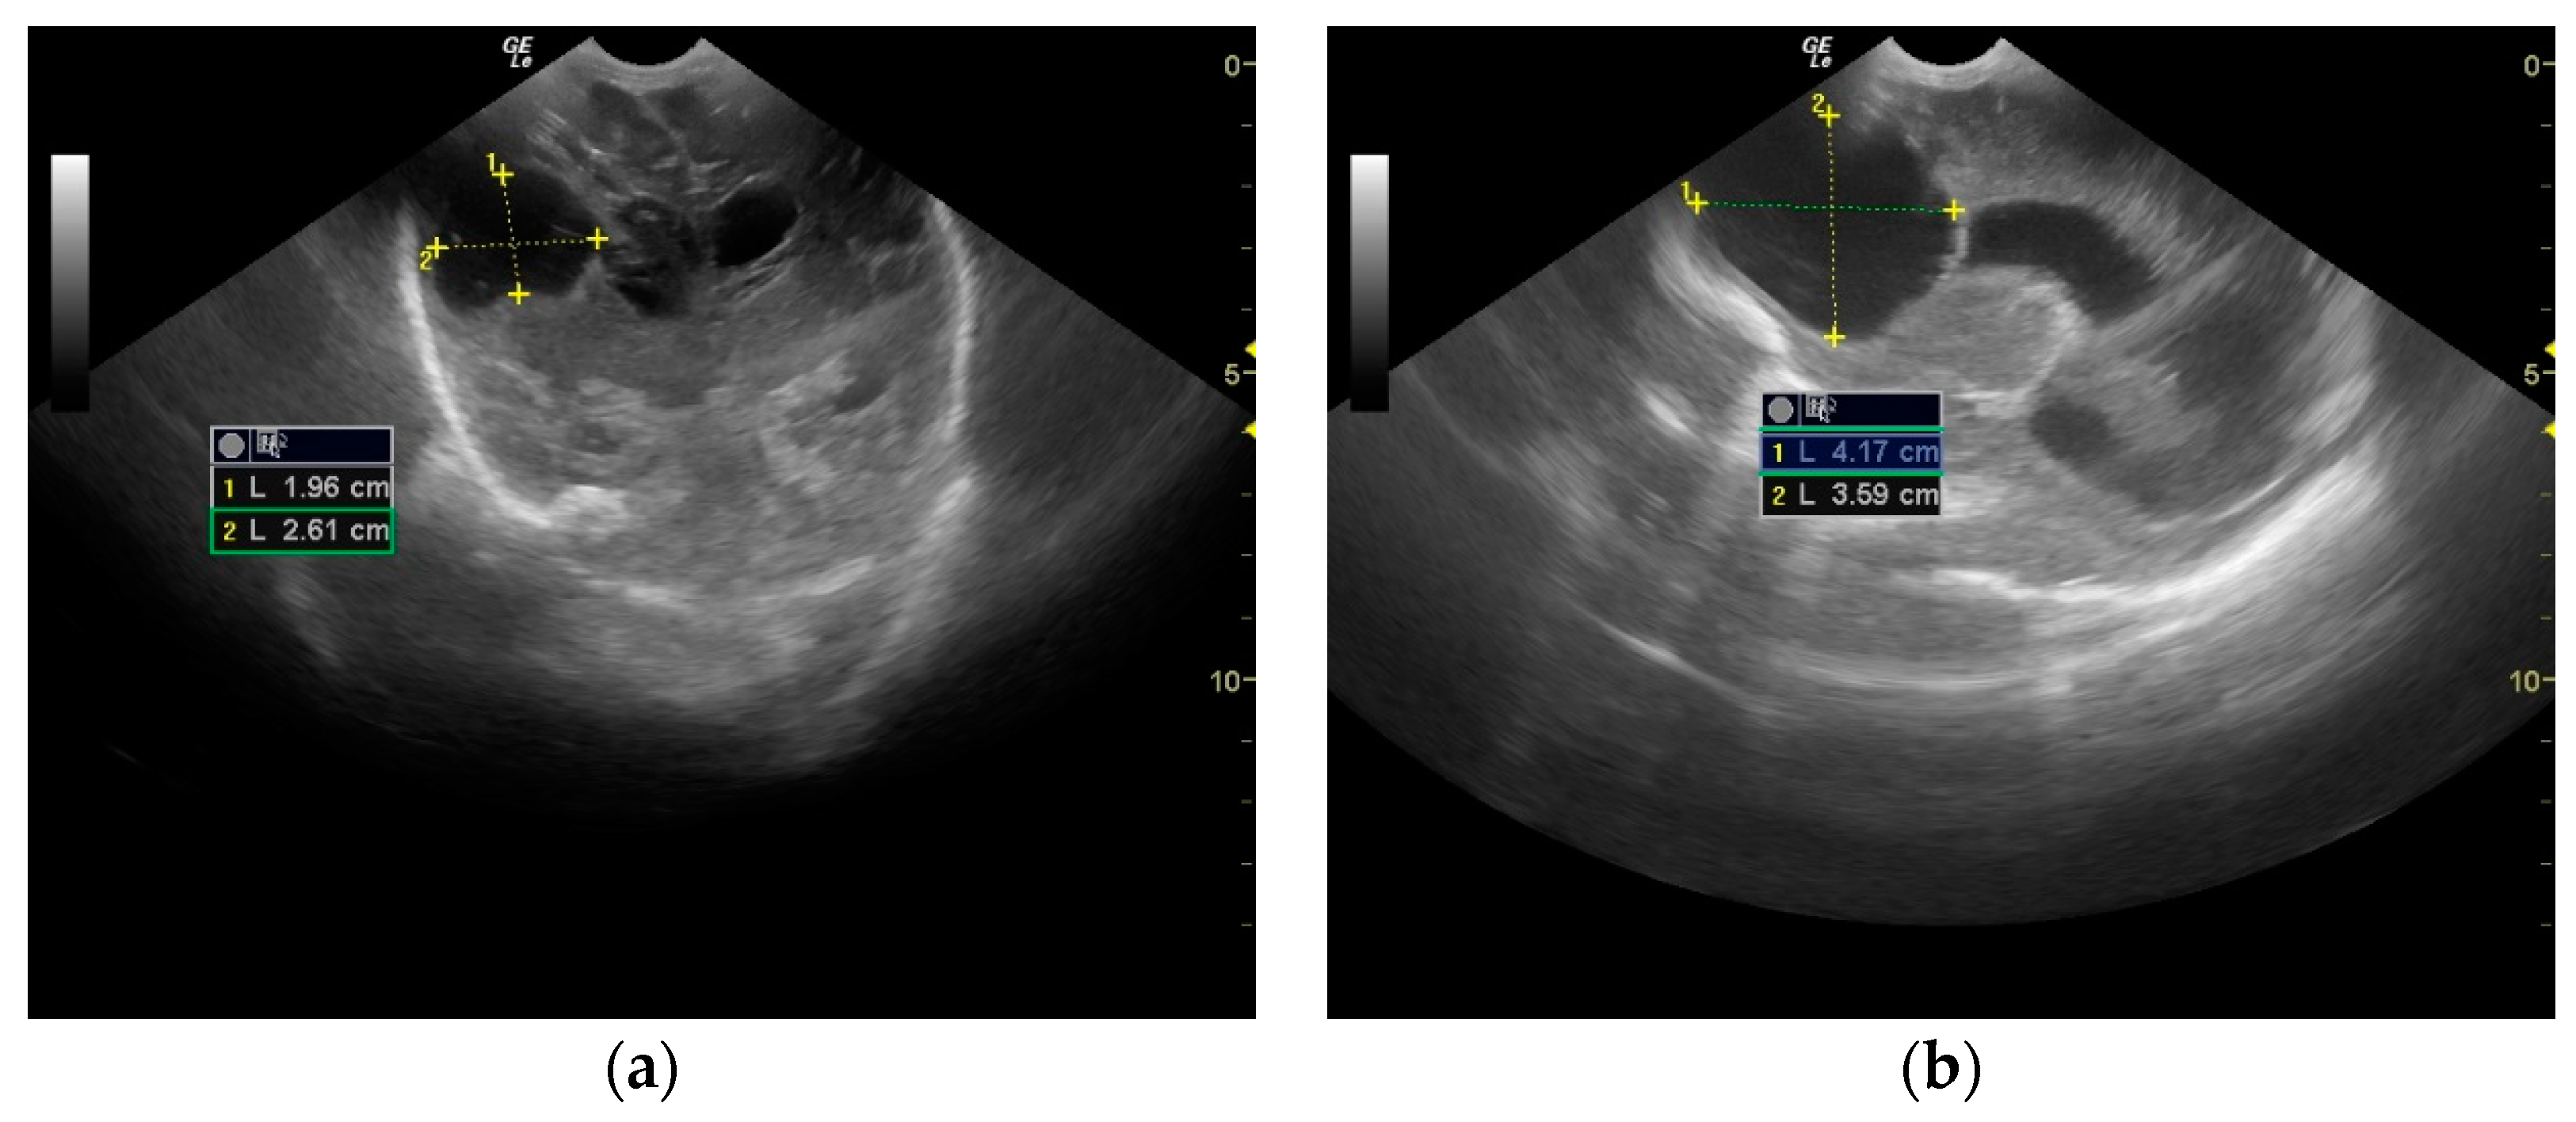

2. Case Presentation